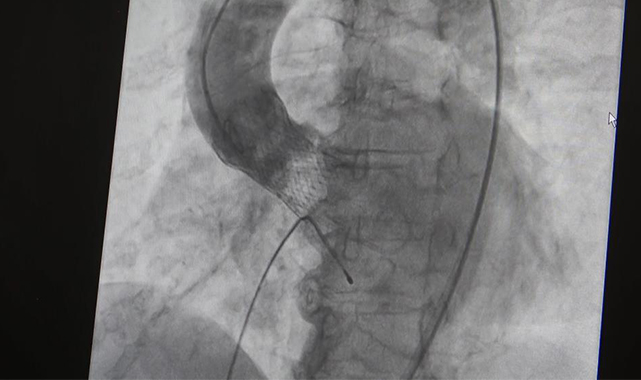

Gürcistanlı vatandaşa yapılan TAVİ işlemi hakkında bilgi veren Uzm. Dr. Ali Ekber Ataş, “TAVİ diye adlandırdığımız, aort kapağına kapalı yolla kapak yerleştirme işlemini Gürcistan’dan gelen hastamız Znulieta Mzhavanadze’ye başarıyla uyguladık. Hastamızın kontrolünü yaptık. Kendisi şu anda oldukça sağlıklı. Bir ayın sonunda kalp kapağında oldukça belirgin iyileşme olmuş ve genel durumu iyi. Yaklaşık 1 ay önce hastayı ilk değerlendirdiğimizde 5-10 metre yürürken bile nefes alamadığını, düz yatamadığını, belirgin çarpıntı ve göğüs sıkışması olduğunu söylemişti. Şimdi bir yakının ifadesiyle kimse artık kendisini tutamaz durumda. Şu an oldukça rahatladı. Günlük ihtiyaçlarını kendisi rahatlıkla karşılıyor. Tabi işlem yaşına uygun şekilde kapalı yolla yapıldığı için hastada herhangi bir ameliyata bağlı travma veya ameliyat izi kalmadı. Günlük hayatına çok çabuk dönmüş oldu. Hastamızı bu konuda gösterdiği sabır ve tedaviye uyum konusunda tebrik ediyoruz” diye konuştu.

Önümüzdeki 10 yıl boyunca ortalama olarak hastanın değişen kapağı ile birlikte normal yaşına uygun olarak bütün fonksiyonlarını yerine getirebileceğini dile getiren Uzm. Dr. Ali Ekber Ataş, “İşine gidebilecek, dolaşabilecek. Kendisi bağımsız şekilde bütün ihtiyaçlarını karşılayabilecek. Hedefimiz de bu zaten. Bu arada kapağını belirli aralıklarla takip ediyor olacağız. Kalp ritminin düzenli gidip gitmediğini, tansiyon dengesizliğinin olup olmadığını da ayrıca takip ediyoruz. Ancak bu hastalarda genellikle ilk aylarda belirgin iyileşme olduğu için kendisinde de eskiye kıyasla daha belirgin bir fonksiyon iyileşmesi olmasını ve günlük hayata hızlıca dönmesini bekliyoruz” şeklinde konuştu.